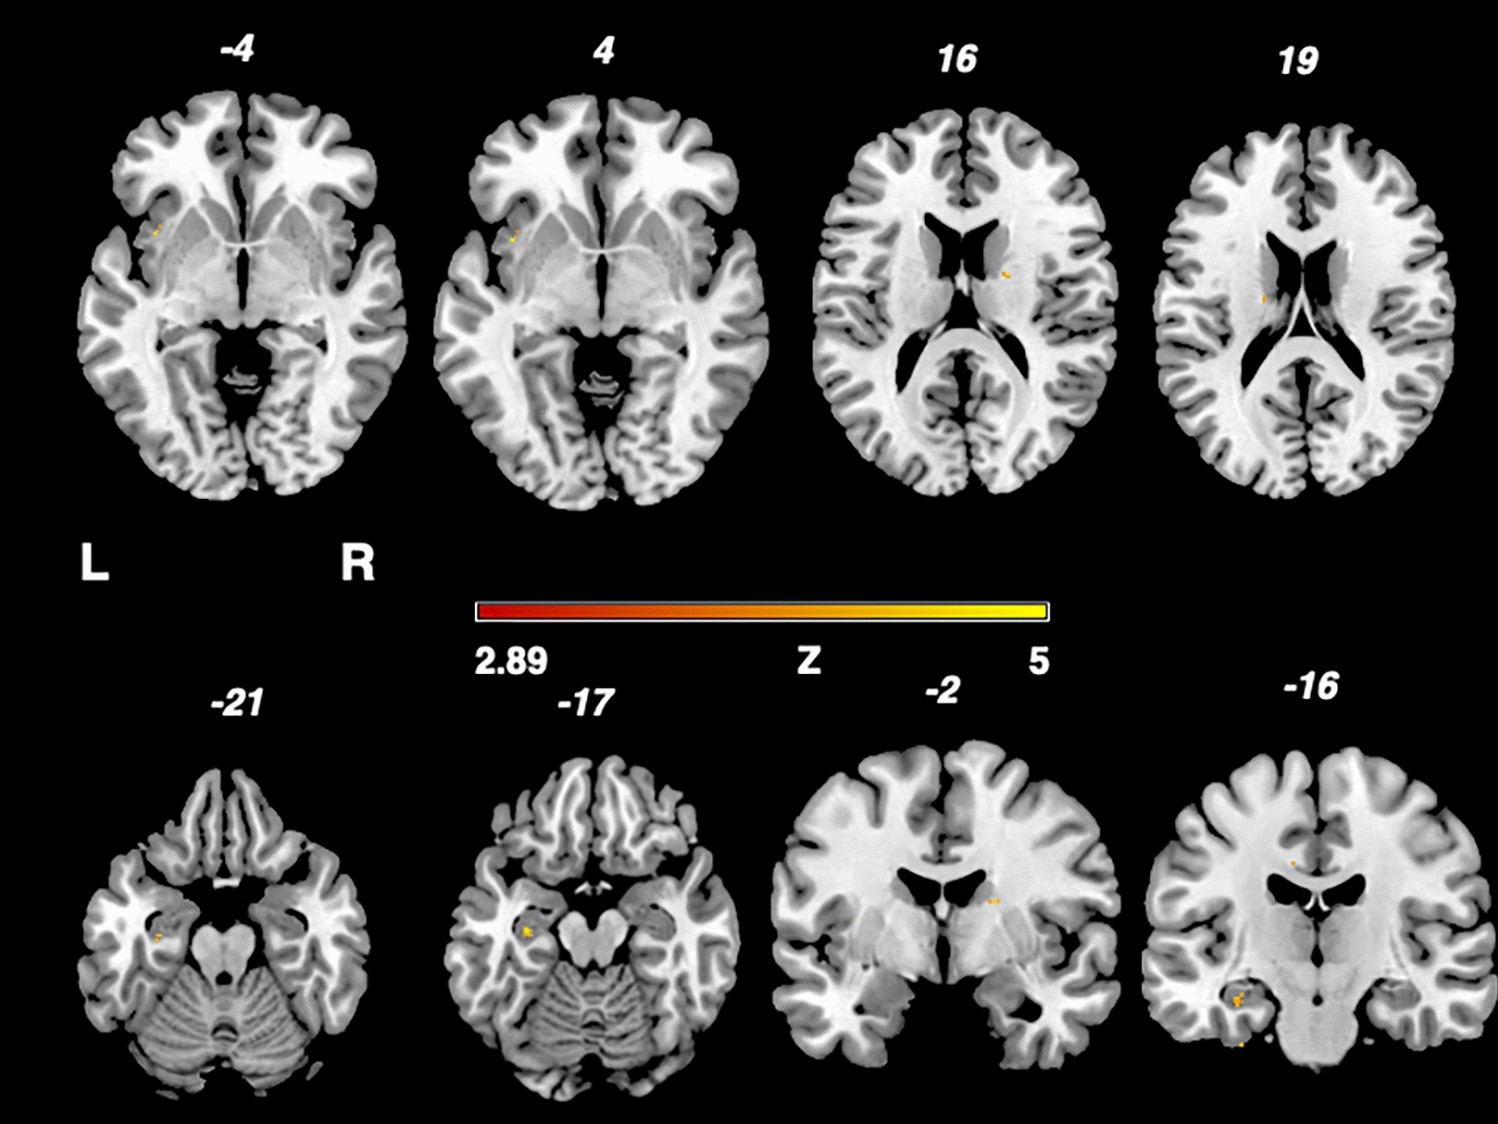

Fig. 2

From: Cerebral lesions in the central pain matrix are associated with headache in multiple sclerosis

Depicition of the nonparametric Liebermeister test results. Associations of lesioned voxels with headache were found in the left insula, left hippocampus and right thalamus. Only voxels that were damaged in at least two patients were included in the Liebermeister test analysis. A family wise error (FWE) correction of p < 0.05 was applied. L left, z z-score, R right.